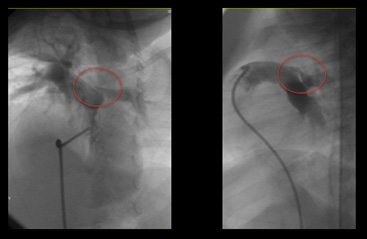

폐동맥지협착

• 스텐트 전 좌폐동맥 입구의 심한 협착

• 스텐트 시술 장면(측면뷰)

• 스텐트 후 늘어난 좌폐동맥(정면뷰)